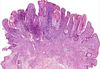

Seborrheic Keratosis

- well demarcated

- mushroom epidermis

- horn cysts(spaces in the tumor filled with keratin)

- benign

- regular looking cells

- wouldn’t see a lot of mitosis

A benign proliferation of keratinocytes

Seborrheic keratosis